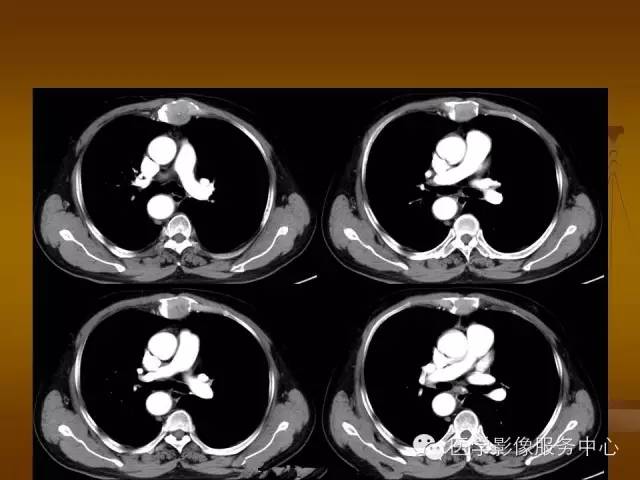

特征性穿凿状、鼠咬状及蜂窝状骨质破坏,边缘清楚,骨质疏松,病理性骨折及软组织肿块等表现,骨质硬化及骨膜反应少见。

骨质破坏区完全为软组织取代,骨质膨胀,边界清楚,常突破骨皮质形成软组织肿块。

增强扫描可见病灶轻中度强化,一般于静脉期达峰值。